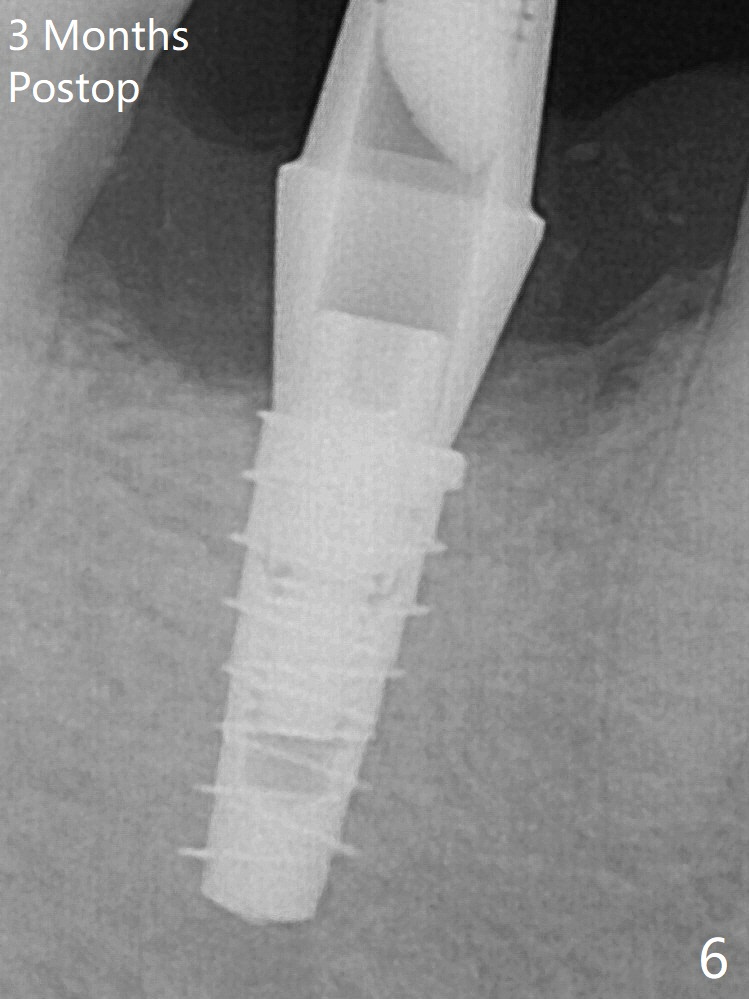

For safety, a 4x9 mm IBS implant is placed with insertion torque 40 Ncm; a 5x5.7(4) mm abutment is immediately placed for an immediate provisional to cover the large socket and keep Vera graft in place (Fig.4 *). Yellow dashed line: apical osteotomy; red dashed line: Mental Loop. Impression is taken nearly 3 months postop (Fig.6). The bone density around the implant increases 7 months post cementation (Fig.8 *).